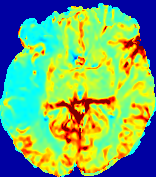

LesionRefer to captionRefer to captionRefer to captionRefer to captionRefer to captionRefer to caption𝐕rgbsubscript𝐕𝑟𝑔𝑏{\bf{V}}_{rgb}Refer to captionRefer to captionRefer to captionRefer to captionRefer to captionRefer to caption𝐕2subscriptnorm𝐕2{\|\bf{V}}\|_{2}Refer to captionRefer to captionRefer to captionRefer to captionRefer to captionRefer to captionRefer to caption3.53.53.52.82.82.82.12.12.11.41.41.40.70.70.70.00.00.0(mm/s)𝑚𝑚𝑠(mm/s)D𝐷DRefer to captionRefer to captionRefer to captionRefer to captionRefer to captionRefer to captionRefer to caption0.0200.0200.0200.0160.0160.0160.0120.0120.0120.0080.0080.0080.0040.0040.0040.0000.0000.000(mm2/s)𝑚superscript𝑚2𝑠(mm^{2}/s)Slice #1Slice #2Slice #3Slice #4Slice #5Slice #6

Figure 3: PIANO feature maps for one stroke patient, where the lesion is located in the left hemisphere. Top row: segmented stroke lesion region (white) on different slices, obtained from ISLES 2017. The corresponding slices for the PIANO feature maps are shown in the following rows.

For a better insight into an estimated velocity field 𝐕𝐕{\bf{V}} and diffusion field 𝐃𝐃{\bf{D}}, we compute the following maps: (1) 𝐕rgbsubscript𝐕𝑟𝑔𝑏{\bf{V}}_{rgb}: Color-coded orientation map of 𝐕=(Vx,Vy,Vz)T𝐕superscriptsuperscript𝑉𝑥superscript𝑉𝑦superscript𝑉𝑧𝑇{\bf{V}}=(V^{x},V^{y},V^{z})^{T}, obtained by normalizing 𝐕𝐕{\bf{V}} to unit length and mapping its 3 components to red, green, blue respectively; (2) 𝐕2subscriptnorm𝐕2\|{\bf{V}}\|_{2}: 222 norm of 𝐕𝐕{\bf{V}}; (3) D𝐷D: scalar field in Eq. 5.

Fig. 3 and Fig. 4 show the PIANO feature maps estimated from two ISLES 2017 patients: all are highly consistent with the lesion in both cases. Details of the blood flow trajectories are revealed in 𝐕rgbsubscript𝐕𝑟𝑔𝑏{\bf{V}}_{rgb} by the ridged patterns and the sharp changes of colors in the unaffected (right) hemisphere, while the flat patterns appearing within the lesion provide little directional information about the velocity and indicate low velocity magnitudes. Velocity magnitudes are more directly visualized via 𝐕2subscriptnorm𝐕2\|{\bf{V}}\|_{2}, from which one can easily locate the lesion where 𝐕2subscriptnorm𝐕2\|{\bf{V}}\|_{2} is low. D𝐷D also indicates lower diffusion values in the lesion, though with less contrast potentially due to the fact that it captures the accumulated effect of CA diffusion at the voxel-level.